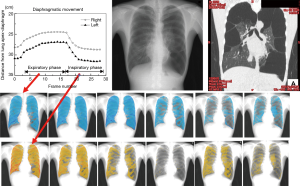

Frontal (anteroposterior) chest X-ray imaging is the most important screening examination among all X-ray examinations. This is because cardiopulmonary images provide diagnostic data that allow an overview of a patient’s general condition. When dynamically imaging the chest, at first, sequential changes caused by respiratory movements, such as movements of the diaphragm, bony thorax, intrapulmonary structures, and cardiac walls, can be analyzed and assessed morphologically. Imaging is done using nearly the same method as conventional frontal chest X-rays, and images a subject’s respiratory process in the order of maximum inspiration to maximum expiration and again to maximum inspiration are obtained. Based on these X-ray images, the degree of diaphragmatic elevation and right–left symmetry, among other parameters, can be analyzed, and as a result, useful diagnostic data can be obtained (20).

Tanaka et al. elucidated that the most important discovery during kinetic chest X-ray examinations is the fact that changes in X-ray translucency (density of black and white) at sites within the lung field during respiration are related to the status of lung ventilation in those sites (2,21-23). When examining density data in the lung field (sequential changes in pixel values), for example, the case shown in Figure 5, synchronized coronal CT images clearly show bilateral bullous emphysema in the same locations and areas of loss can be seen as changes in the density of sequential X-ray images (lower two-stage sequential images). In normal cases, such areas of loss and sites with irregular density changes are not observed. In other words, in intrapulmonary sites where there are no abnormalities in ventilation, density changes are not seen. In normal intrapulmonary sites, X-ray translucency increases during the inspiratory phase and images become darker and translucency decreases during the expiratory phase and images become lighter. This is because the density per unit volume of intrapulmonary structures, such as blood vessels and bronchi, at any given site decreases during the inspiratory phase and increases during the expiratory phase.

For dynamic chest radiography, spatial and temporal resolutions and exposure dose have to be balanced using optimal system settings. The imaging rate should be greater than 7.5 frames per second (fps) for an accurate evaluation of cardiac function. For respiratory function, an imaging rate lower than 7.5 fps is acceptable, considering the exposure dose. The entrance surface dose for the detector was approximately 1.9 mGy for 14 s imaging performed at 120 kV, 50 mA, 2.5 ms, 15 fps, and 2.0 m source-image receptor distance. Digital image parameters were 2,688×2,688 matrix, 160 micron pixels, and 4,096 gray level (2).